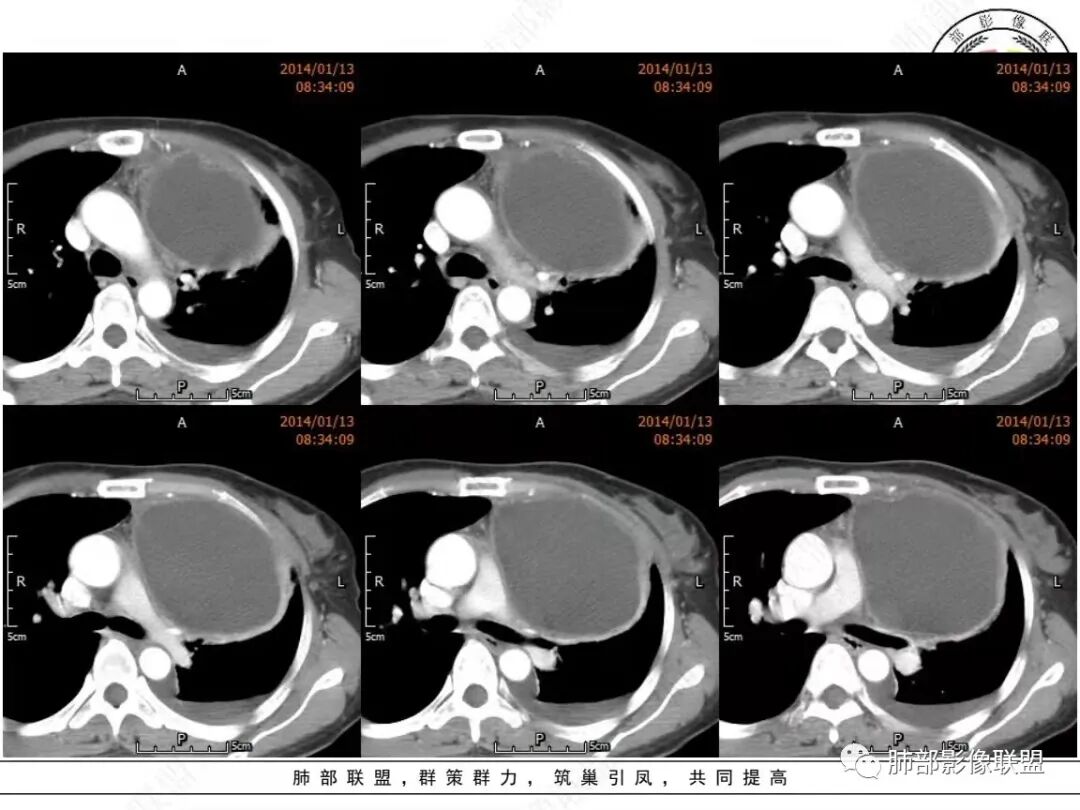

真人:中老年女性,左前纵隔囊实性占位,边界比较清晰,肺组织受压改变,考虑良性病变,囊性胸腺瘤?鉴别囊性畸胎瘤

宇宙:左前中纵隔囊性肿块伴壁结节,结节强化,边缘光整,邻近血管及左侧支气管受压,左侧胸水,考虑囊性胸腺瘤

邢瑞欣:老年女性,定位前纵隔,近圆形囊性低密度影,壁厚有软组织影,强化明显,定性良性肿瘤,囊性畸胎瘤,囊肿,鉴别,转移瘤,胸腺瘤

空格:病灶的后内下增厚的包膜未见连续,纵隔脂肪浑浊密度增高、左侧胸腔积液,开始出现前胸后背的疼痛,完全可以用囊性灶破裂,引起化学刺激来解释。  不然看着软趴趴的病灶,既不可能是转移或侵犯胸膜引起的积液,也不像单纯纵隔或胸腺脓肿,因为白细胞不高。囊肿破裂是最好的解释。  这点就是手术指征。   定性  良性。    分析下来源:  1 这个部位常见的囊实性病灶有 囊性畸胎瘤、胸腺瘤出血囊变、支气管囊肿伴感染,淋巴管来源(前无神、后无皮,神经源性肿瘤不用考虑)。从发病年龄看,胸腺瘤>畸胎瘤,从壁结节强化后面丝丝拉拉的强化看,畸胎瘤可能大。两者都可以接受。综合囊性畸胎瘤破裂大于胸腺瘤出血囊变

衡妈:老年女性,定位是关键。左前中纵隔囊实性占位,囊性为主,囊壁厚薄不均,局部内壁可见壁结节,增强中等强化。考虑囊性畸胎瘤,鉴别胸腺瘤。

Dr. xiao:成熟囊性乏脂性畸胎瘤可能,增强只看到一期(动脉晚期),如果能有两期,能看到囊壁结节动态增强方式,确定囊变结节以发育成熟的畸形血管团为主,影像上出现静脉期强化程度的进一步加强,就更有把握

放射线:左侧纵隔囊性占位,可见壁结节,与纵膈结构分界不清,左肺组织受压,左侧内乳动脉增粗,壁结节明显强化,左侧胸腔积液,考虑囊性畸胎瘤,鉴别胸腺瘤?甲状腺来源肿瘤?